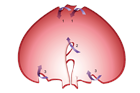

1. 嘔吐、腹痛、腹部膨満、便秘などを主訴に受診した場合には、腸閉塞の診断を行い、その原因として、内ヘルニアを念頭に置いておく必要がある。内ヘルニアによる絞扼性腸閉塞は重篤化するため、早期診断が重要である。早期診断には造影CTが有用であるため、行うことが勧められる(推奨度1 O)

1. 内ヘルニア・横隔膜ヘルニアと診断がつき次第、手術適応である。緊急的に行うか、待機的に行うかについては、造影CTで腸閉塞の状態を把握する必要がある。陥入した腸管を整復し、ヘルニア門を閉鎖もしくは開放する手術を行う(推奨度2 C)

1. 食道裂孔ヘルニアのある場合には胃食道逆流症(GERD)の合併率が高い。胃液の逆流による逆流症状を認め、治療はまず胃酸分泌抑制としてPPIによる治療を行う。内服治療だけでなく、食事指導、生活指導も重要である(推奨度1 M)